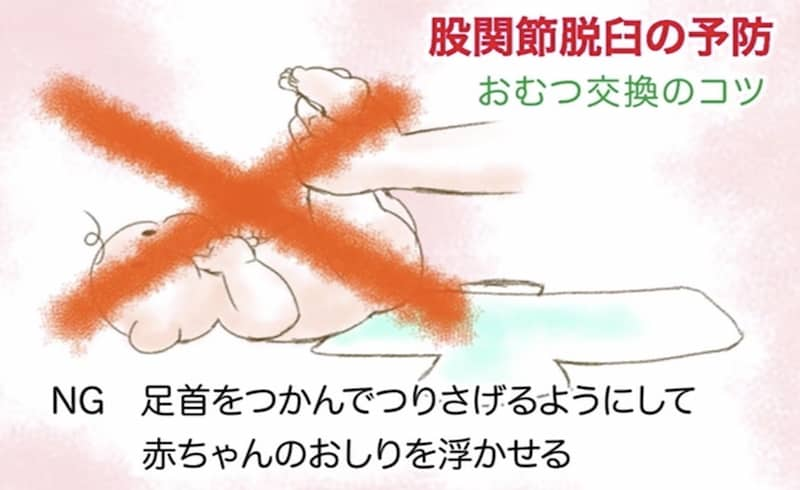

① おむつ

便漏れを防ぐために両サイドのテープの幅が広いものがありますが、これをきつく止めると股関節を伸ばした状態で固定されてしまうので、サイドテープの幅は狭いものを選び、きつく締めないようにしましょう。おむつ交換の時には、足先から持ち上げるのではなく、お尻の下に手を入れて持ち上げるようにしましょう。